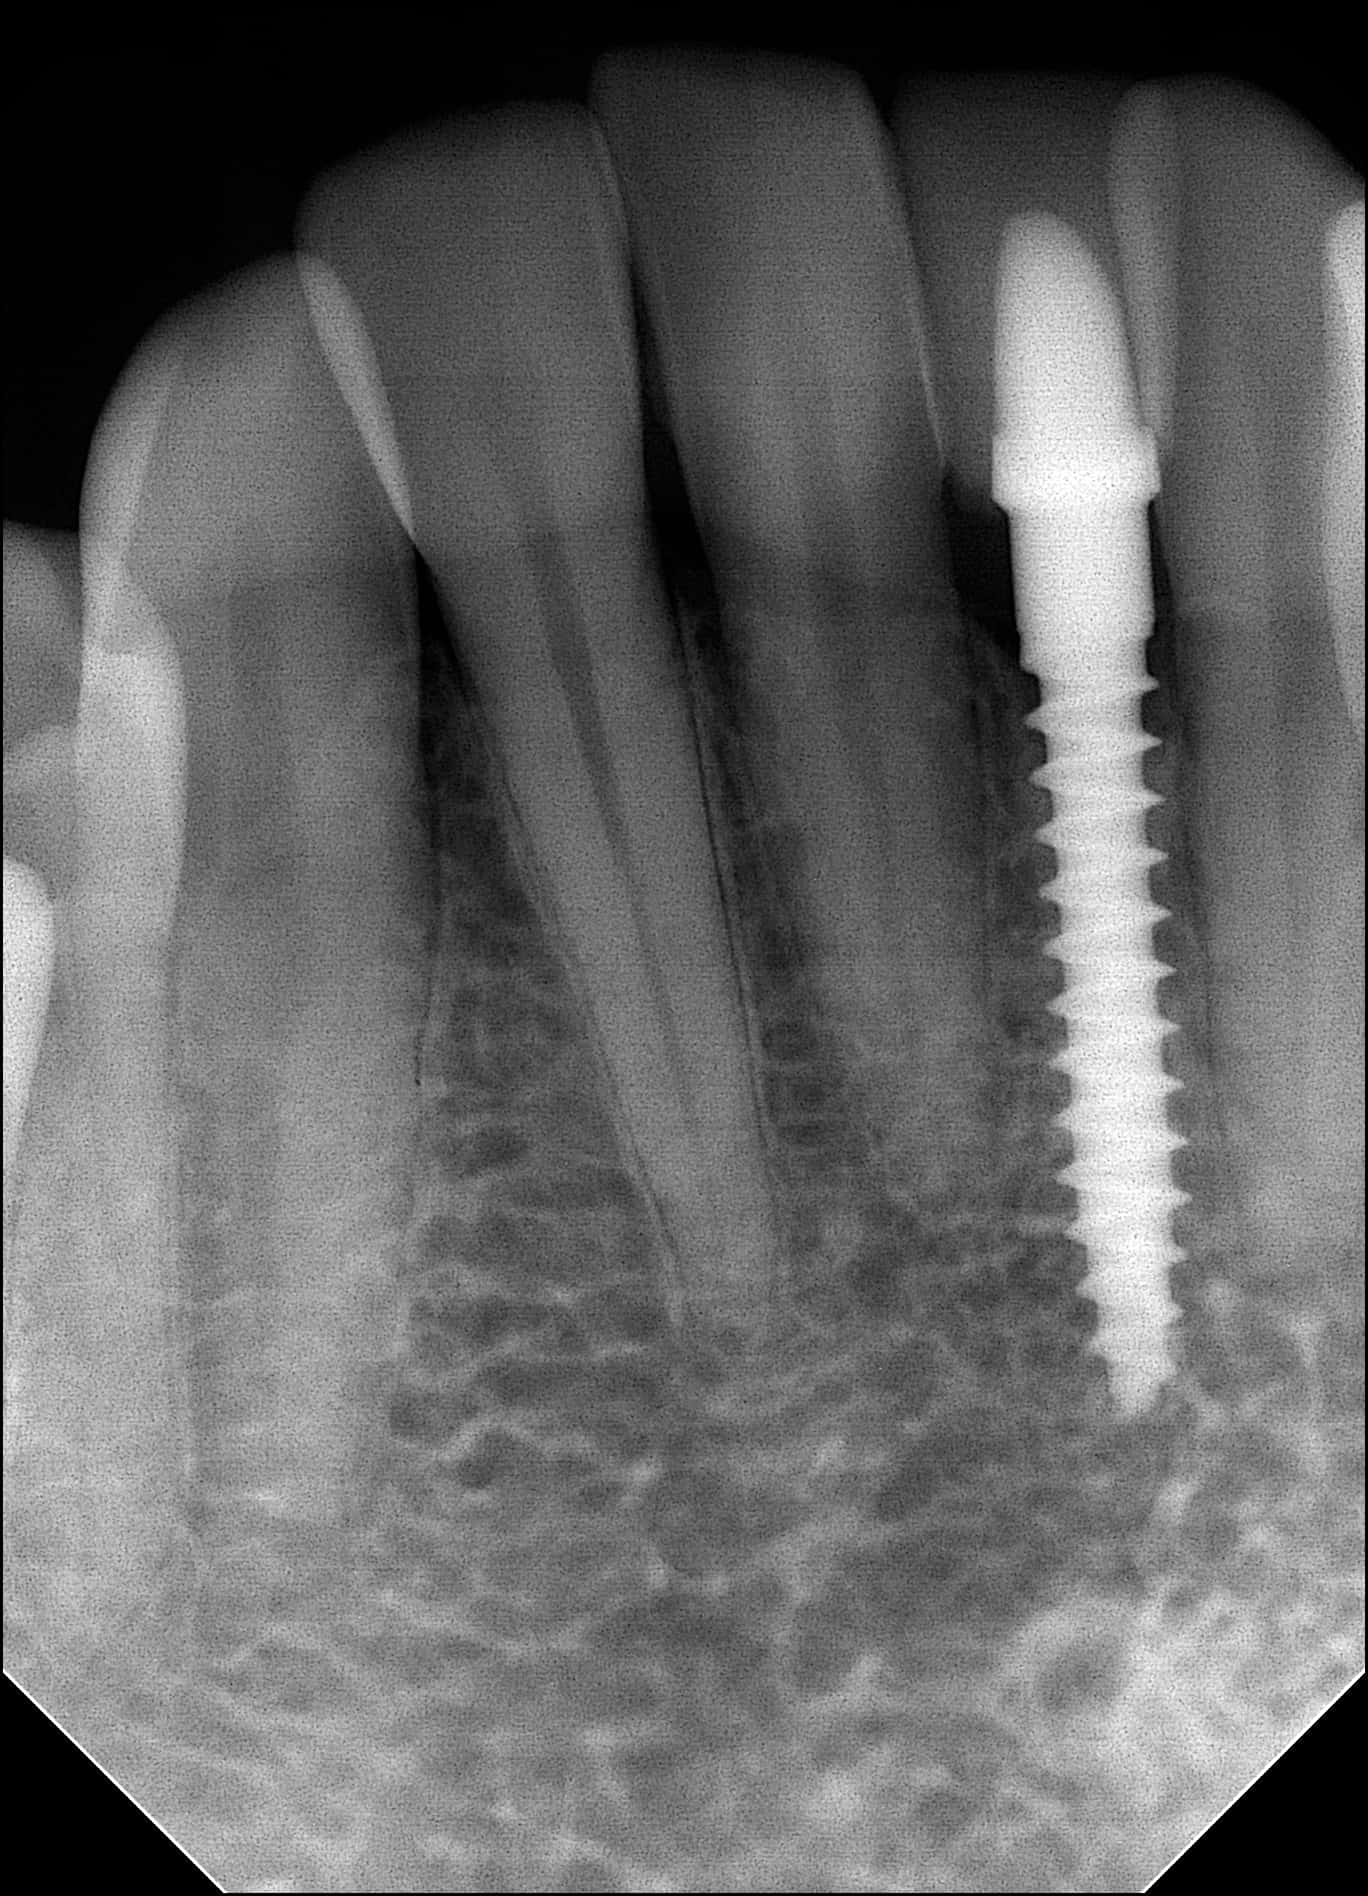

An x-ray taken three years later shows the healthy implant has integrated well with the bone around it. The implant looks stronger than ever and our patient is happy with the results.

Replacing a Lower Incisor with a Thin Dental Implant

In August of 2011, a young cardiologist stopped by our office. One of his lower incisors was congenitally missing, it never grew in. He has gone for numerous consultations, every dentist has previously told him there was not enough room to place a dental implant. He was offered all sorts of options, such as a removable flipper, a bridge, he was even asked to extract another healthy tooth to make room for a conventional implant. He did not like any of those treatment options. He just wanted his missing tooth replaced without damaging any of his other teeth.

Dr. Mann placed a mini-dental implant without any sutures, no cutting of the gums, and with no discomfort. The entire appointment took less than 30 minutes and the patient left the office with a temporary tooth.

Two weeks after the implant was placed, the final crown was cemented. Now, our patient can once again smile with confidence. Mini-dental implant in this situation was the best way we could achieve such a beautiful result.